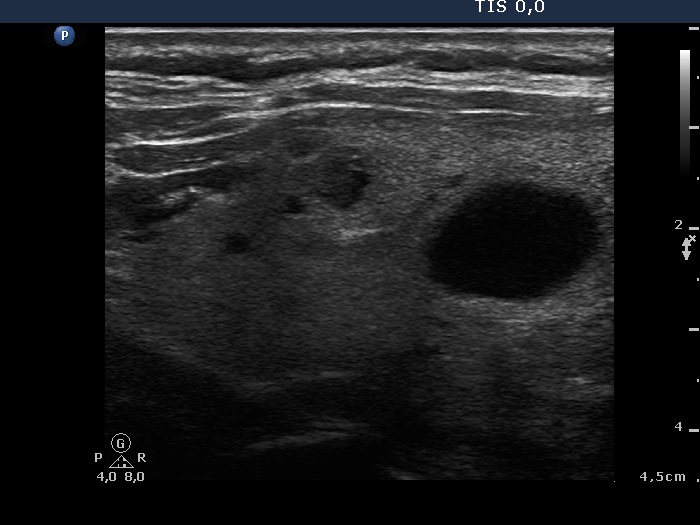

Study on 100 consecutive patients with thyroid nodule - case 056 (ultrasonographic picture 6)

Left lobe, longitudinal view.